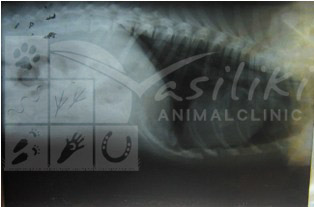

Έγινε ακτινογραφία θώρακος όπου διαπιστώθηκε ότι ο Λάκης είχε υποστεί έναν σοβαρότατο τραυματισμό , πιθανότατα από αυτοκίνητο, και είχε υποστεί ρήξη του διαφράγματος. Σαν αποτέλεσμα, μέρος των ενδοκοιλιακών του οργάνων ( συκώτι, στομάχι, εντερικές έλικες) είχαν εισέλθει στον θώρακά του και δυσκόλευαν την αναπνοή και καρδιακή λειτουργία του.

ΑΚΤΙΝΟΓΡΑΦΙΕΣ ΠΡΙΝ ΚΑΙ ΜΕΤΑ ΤΗΝ ΕΠΕΜΒΑΣΗ

ΠΡΙΝ